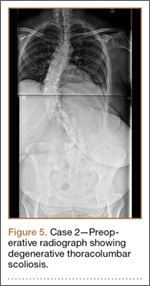

Clinical Presentation. A 51-year-old woman presented to the outpatient clinic with progressive low back pain and decompensation due to degenerative adult scoliosis. Her surgical history was significant for an uneventful Caesarean section. Her medical history was significant for borderline hypertension and obesity (body mass index, 34.4). The radiographic examination showed an S-shaped thoracolumbar curve from T4 to L4 (Figure 5).